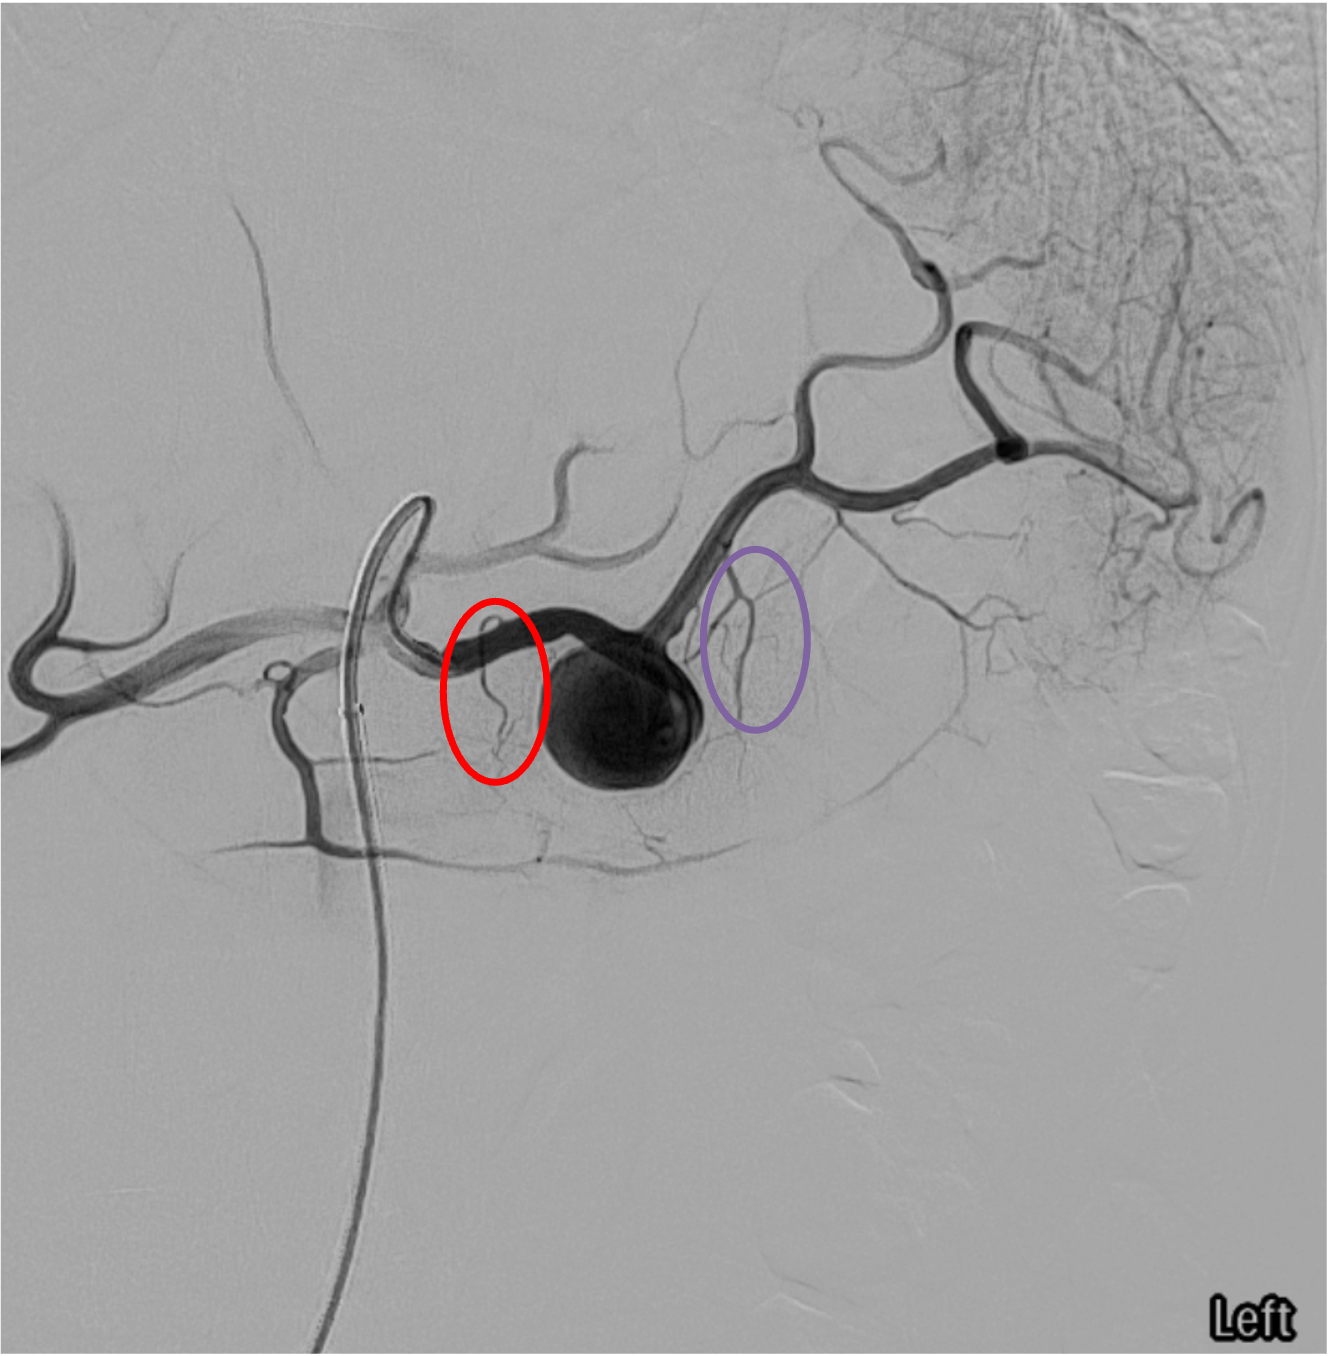

Splenic artery anatomy — key branching landmarks for proximal embolization targeting.Splenic angiogram — dorsal pancreatic artery (red) and pancreatica magna (purple); proximal embolization target is distal to these branches.

Key branches: dorsal pancreatic artery (proximal), pancreatica magna (mid), short gastric arteries (distal), left gastroepiploic, and terminal splenic branches at the hilum.

For proximal embolization: deploy distal to the dorsal pancreatic and pancreatica magna origins but proximal to the hilum — preserves pancreatic blood supply and allows collateral flow from short gastrics and gastroepiploics to maintain splenic perfusion at reduced pressure.